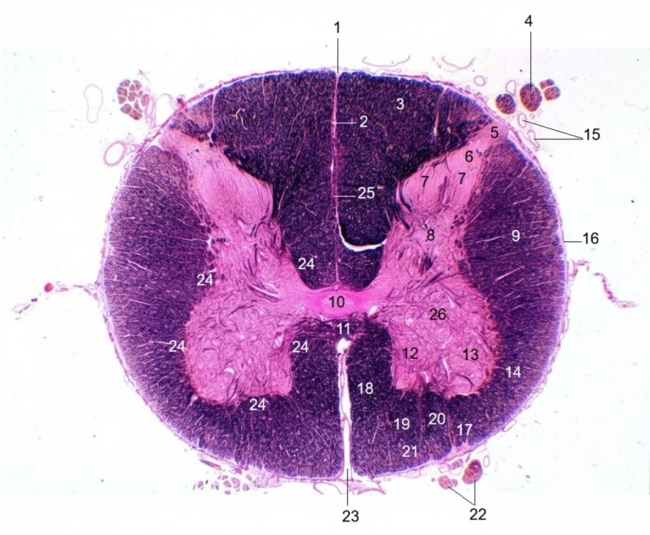

1. Dorsal median sulcus

2. Dorsal median septum

3. Gracile fasciculus

4. Dorsal root

5. Dorsolateral tract of Lissauer

6. Dorsal marginal nucleus (Lamina I)

7. Substantia gelatinosa (Lamina II)

8. Nucleus proprius (Lamina III, IV)

9. Lateral corticospinal tract

10. Central canal with central gray matter

11. Ventral white commissure

12. Medial motor nuclei (Lamina IX)

13. Lateral motor nuclei